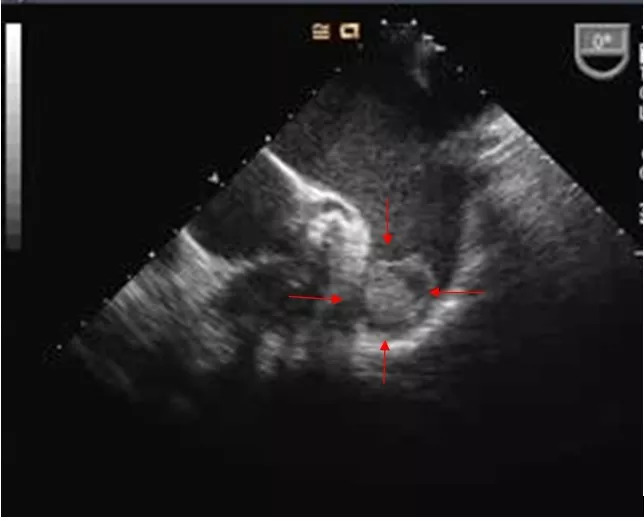

上图中红色箭头所指为左心耳血栓